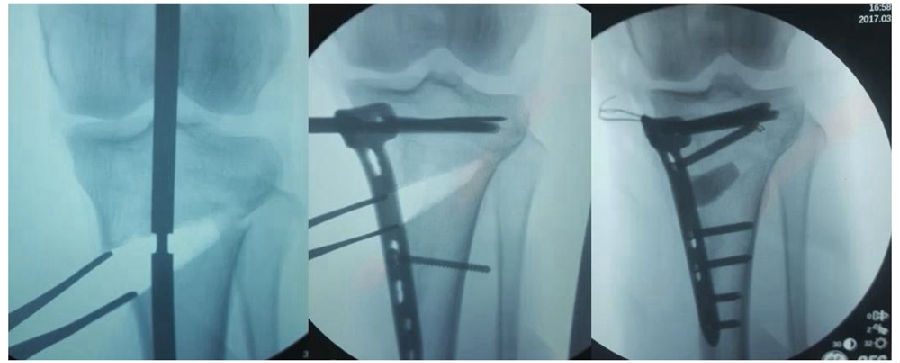

(3)Ⅲ型骨折

首先要把截骨撑开钳拿下来,此时骨折端会自动复位,然后再由外向内侧打入一颗拉力螺钉,将胫骨平台做临时固定,然后再进一步的用摆锯锯或是用骨刀打,保留1cm的合页,最后再进行撑开,做内固定。同样要求患者做结构植骨加延迟负重。

截骨偏前,截骨线过短;Ⅲ型骨折;保留1cm合页

结构植骨,外侧拉力钉固定